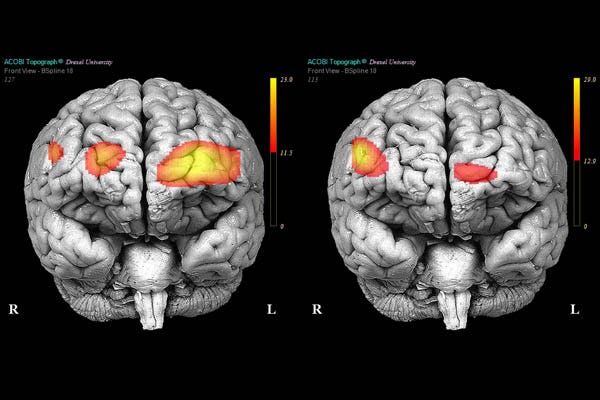

Its All In Your Head: Borderline Personality Disorder and the Brain, by Kevin Redmayne, Invisible Illness